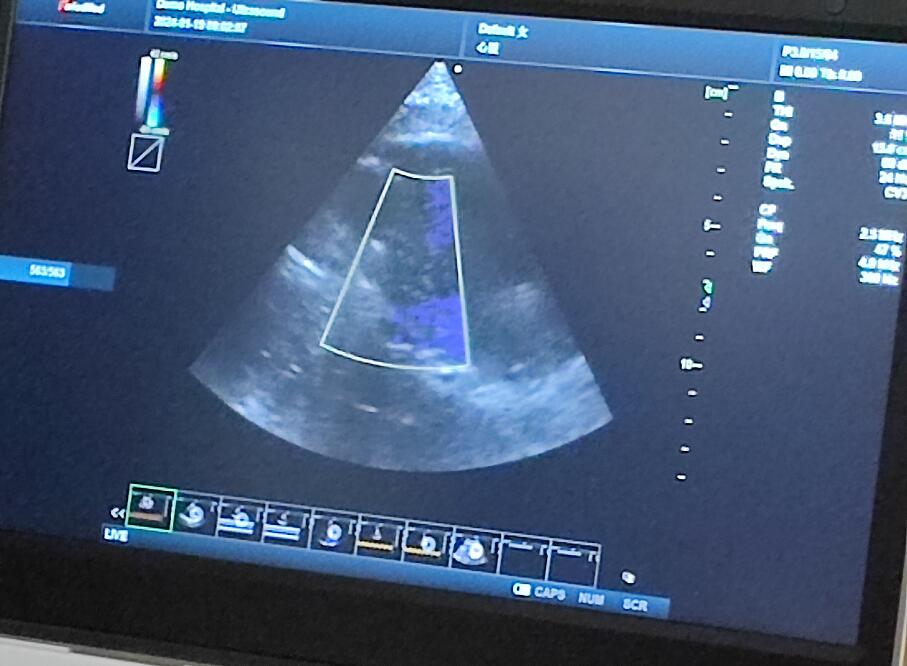

當(dāng)天的超聲培訓(xùn)現(xiàn)場氣氛熱烈非凡,來自普邁思醫(yī)療事業(yè)部的同仁們紛紛積極參與,滿懷期待地聚集在講臺(tái)周圍,他們的眼神充滿了對新知識的渴望和對技術(shù)提升的執(zhí)著追求。老師身邊里三層外三層圍滿了學(xué)員,大家或是聚精會(huì)神聆聽講解,或是踴躍提問,交流互動(dòng),濃厚的學(xué)習(xí)氛圍讓整個(gè)場地顯得熱鬧非凡,盡管空間狹小,但阻擋不住的是每一位參與者內(nèi)心深處對于專業(yè)技能提升的決心與毅力。

授課的專家老師被這股澎湃的學(xué)習(xí)熱情深深打動(dòng),她的臉上洋溢著欣慰和鼓舞的笑容。面對這樣一群如饑似渴的學(xué)子,老師更是傾盡全力,毫無保留地將自己豐富的臨床經(jīng)驗(yàn)和深厚的專業(yè)理論知識悉數(shù)傳授,詳細(xì)解答每一個(gè)問題,用心指導(dǎo)每一次操作演練。她表示,普邁思醫(yī)療事業(yè)部團(tuán)隊(duì)展現(xiàn)出的這種敬業(yè)精神和積極向上的風(fēng)貌讓她深受感染,還給予了他們高度評價(jià)和嘉許。